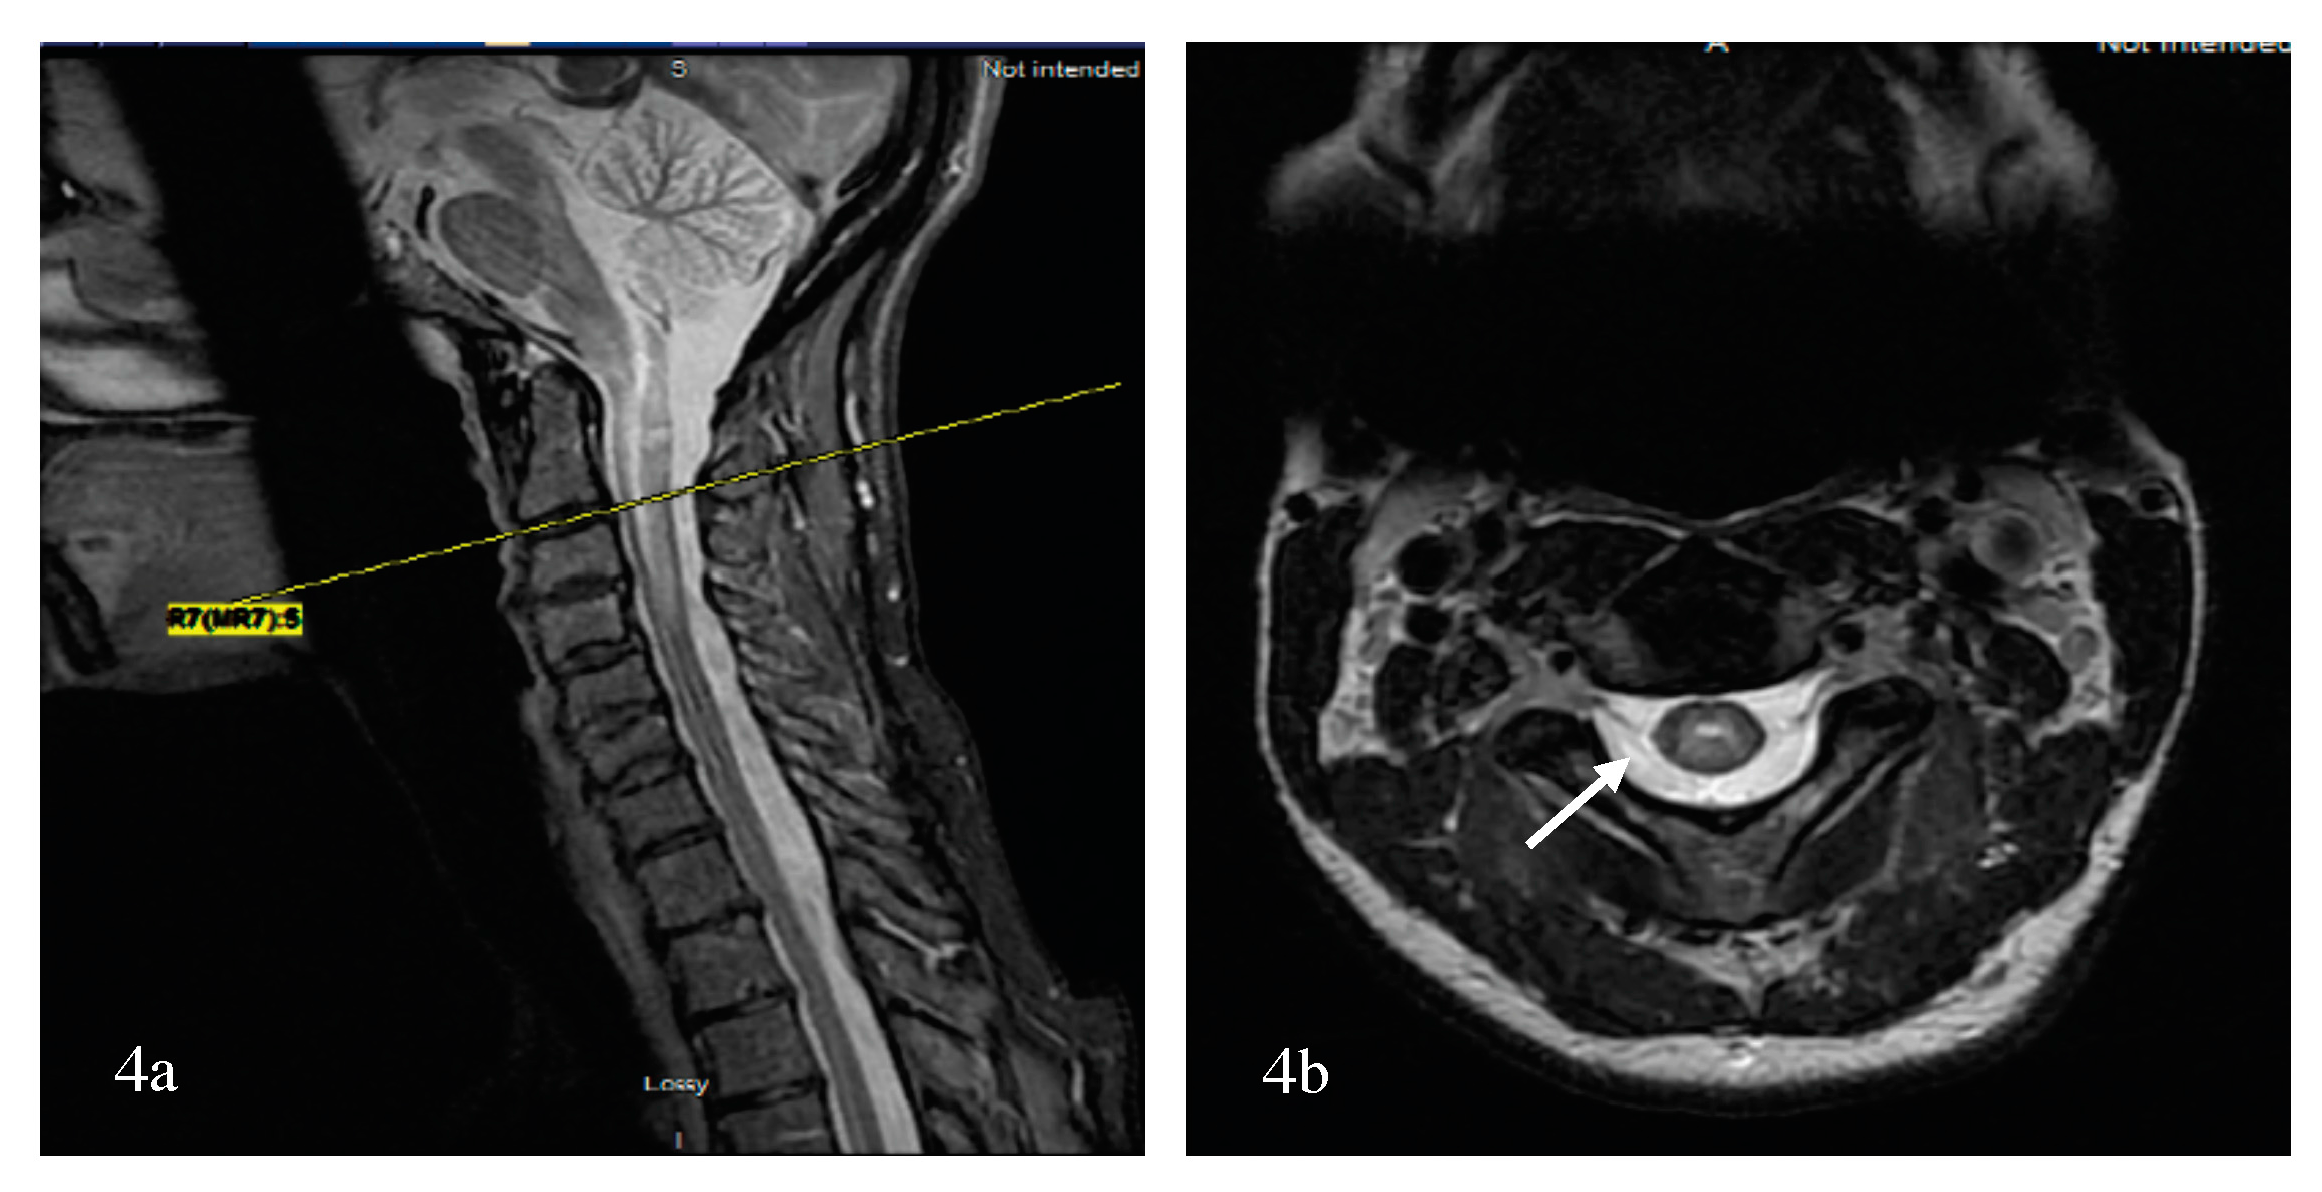

- Cai, W.; Tan, S.; Zhang, L.; Shan, Y.; Wang, Y.; Lin, Y.; Zhou, F.; Zhang, B.; Chen, X.; Zhou, L.; et al. Linear lesions may assist early diagnosis of neuromyelitis optica and longitudinally extensive transverse myelitis, two subtypes of NMOSD. J. Neurol. Sci. 2016, 360, 88–93. [Google Scholar] [CrossRef] [PubMed]

- Yonezu, T.; Ito, S.; Mori, M.; Ogawa, Y.; Makino, T.; Uzawa, A.; Kuwabara, S. “Bright spotty lesions” on spinal magnetic resonance imaging differentiate neuromyelitis optica from multiple sclerosis. Mult. Scler. 2014, 20, 331–337. [Google Scholar] [CrossRef] [PubMed]

- Pekcevik, Y.; Mitchell, C.H.; Mealy, M.A.; Orman, G.; Lee, I.H.; Newsome, S.D.; Thompson, C.B.; Pardo, C.A.; Calabresi, P.A.; Levy, M.; et al. Differentiating neuromyelitis optica from other causes of longitudinally extensive transverse myelitis on spinal magnetic resonance imaging. Mult. Scler. 2016, 22, 302–311. [Google Scholar] [CrossRef] [PubMed]